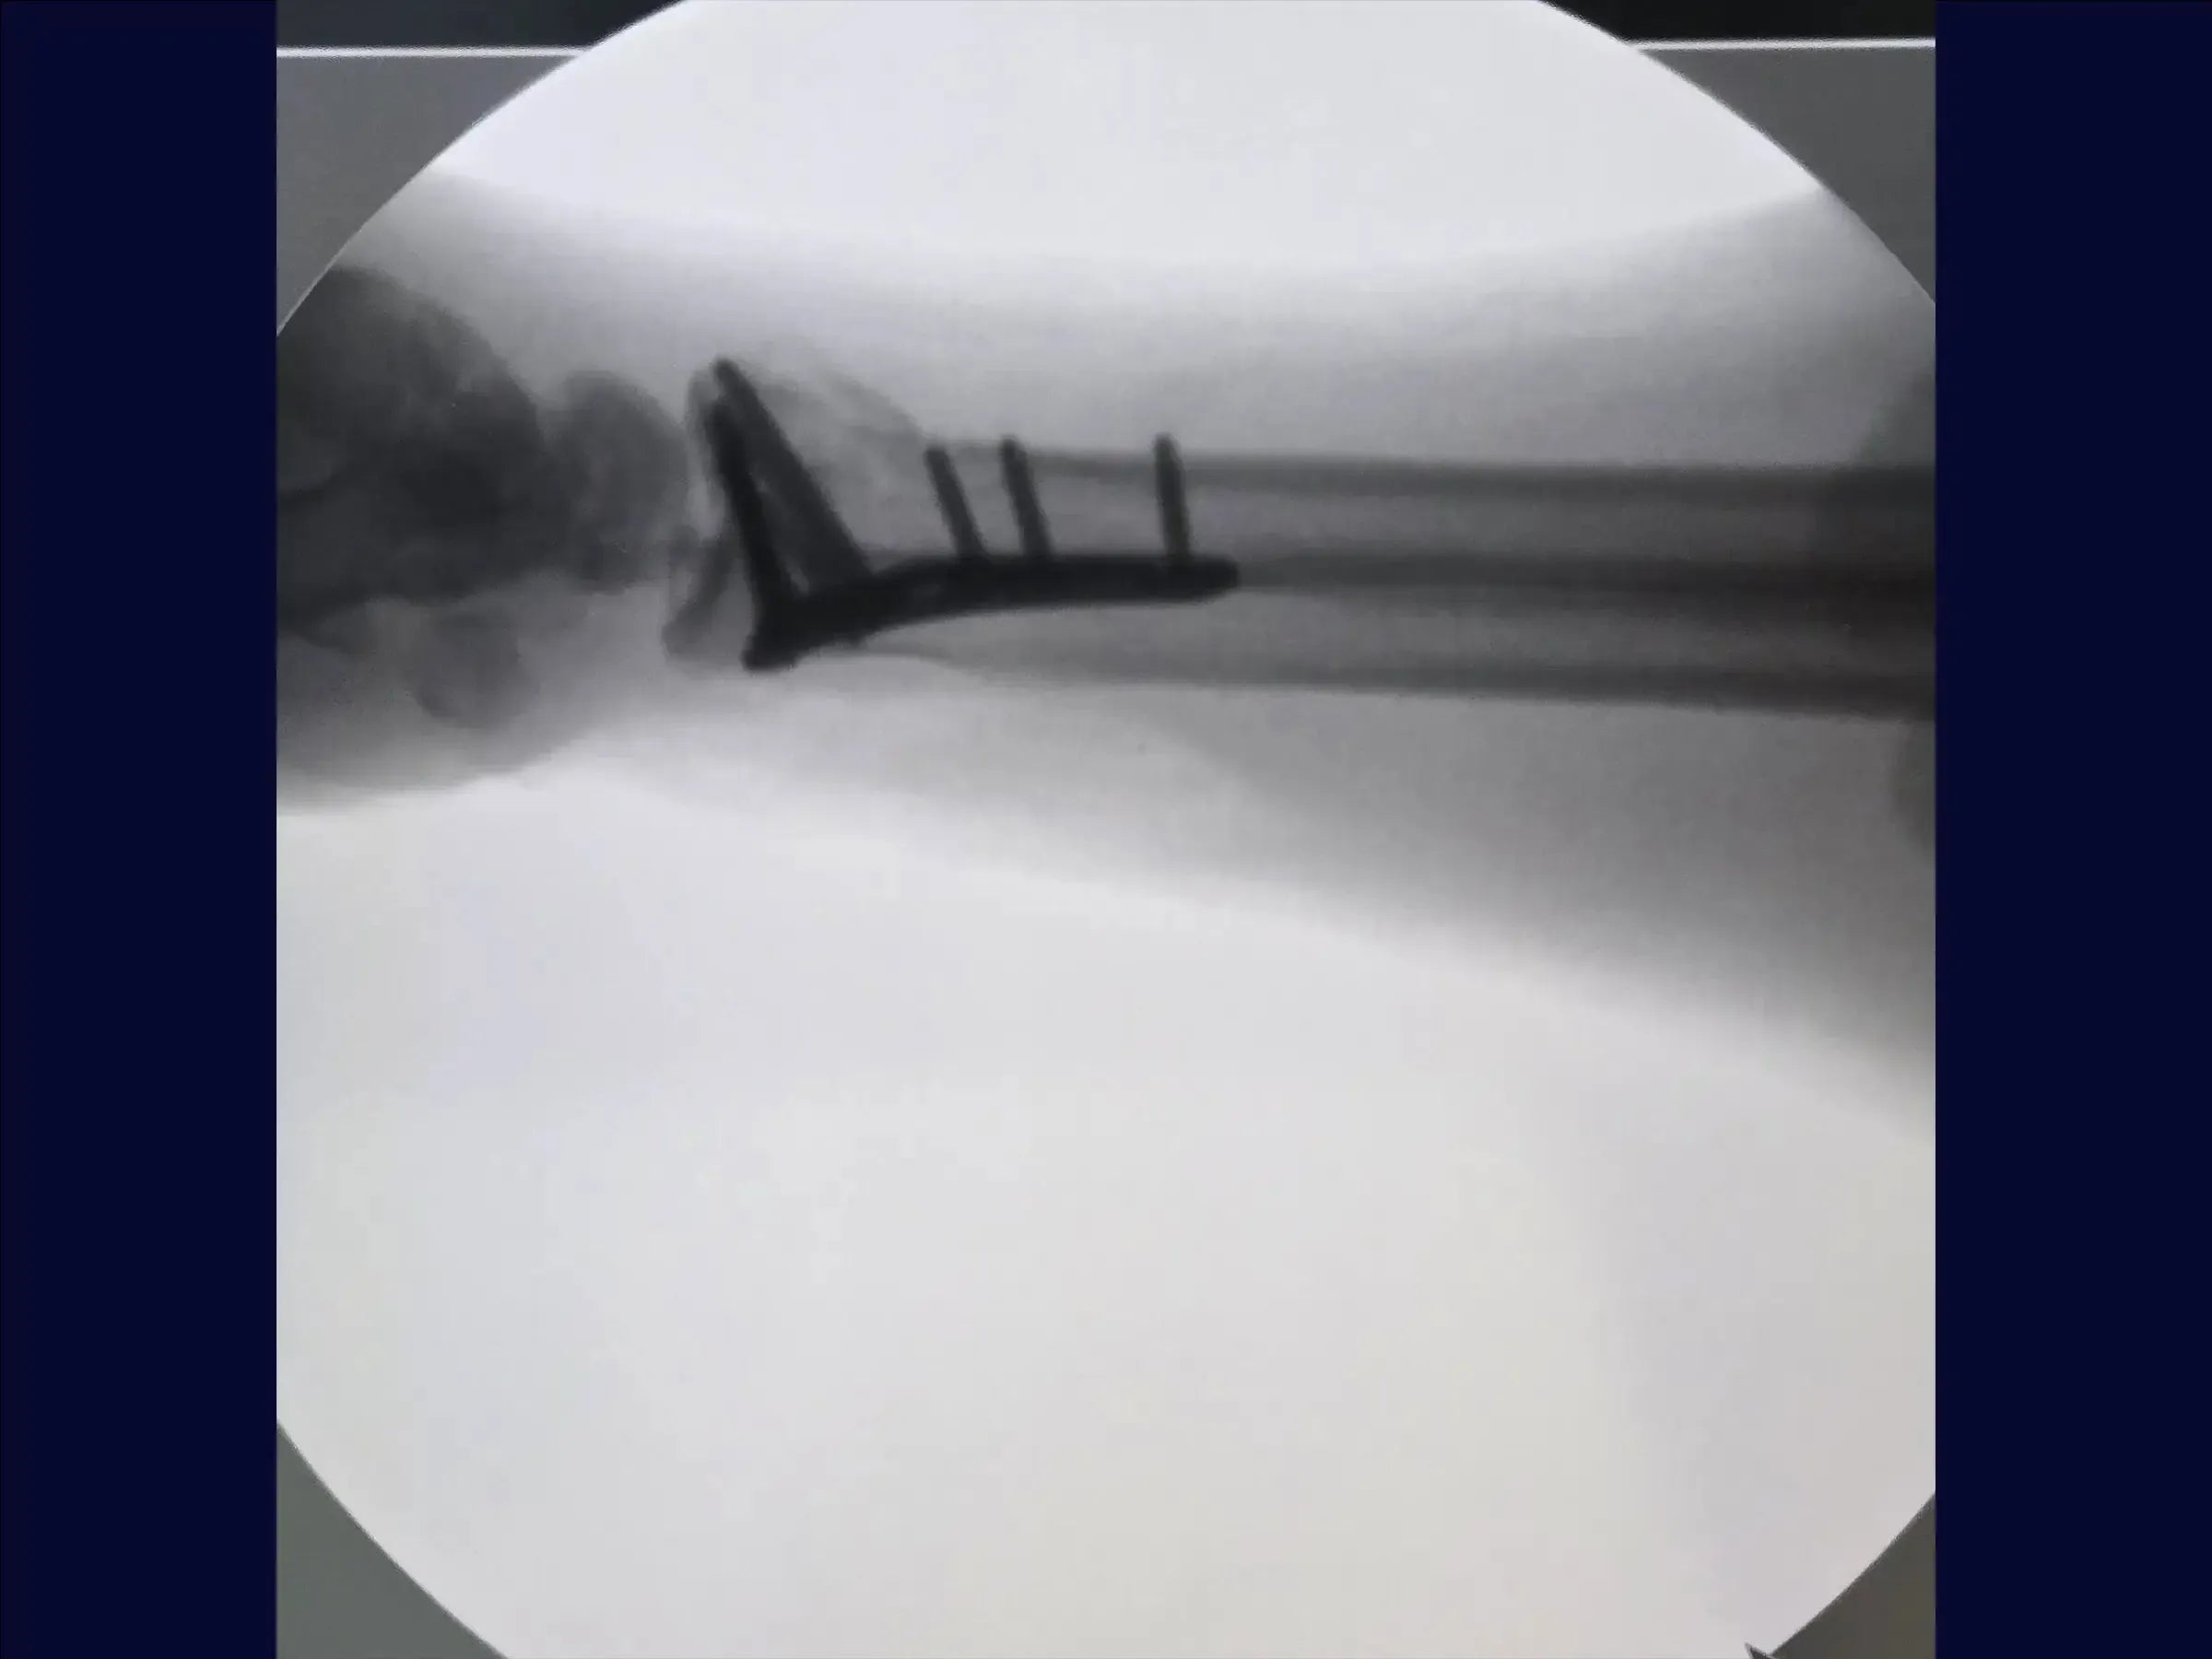

- Exposição do Rádio e Implantação da Placa: O rádio é exposto, e um descolador é utilizado para preparar o leito da placa. Com a fratura já reduzida pela fixação provisória, a colocação dos parafusos deve respeitar a inclinação radial para evitar que fiquem intra-articulares. É recomendado manter a redução manualmente ou usar fios adicionais para evitar perda de redução.

- Fechamento e Resultados: O acesso através do pronador quadrado é suturado para cobrir a placa. O resultado final é satisfatório, com parafusos bem posicionados, inclinação radial mantida e fratura bem fixada. O fechamento é realizado por planos até a pele.